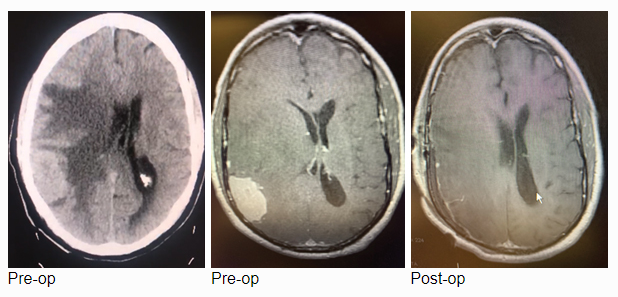

MRI with gadolinium confirmed the likely diagnosis of convexity meningioma, a benign neoplasm of the meninges. Given the location of the tumor, angiography and embolization were deemed unnecessary prior to resection. Stereotactic c-guided craniotomy was performed by Dr. Jonathan Brisman and the tumor was carefully excised from the surrounding brain. A gross total resection was achieved. He was discharged from the hospital to his home, neurologically intact with a slow improvement of his gait. Postoperative MRI showed no evidence of residual tumor.

Pathologic analysis revealed a meningothelial tumor consistent with a meningioma with atypical features (immunocytochemical positive staining for vimentin, EMA, and Ki67 at 23%), and the lesion was graded an Atypical Meningioma, WHO grade 2. Neuro-oncology consultation was obtained and a decision was made to monitor conservatively, with radiation therapy indicated for tumor recurrence only. The patient has since returned to normal neurologic function with no evidence of tumor recurrence